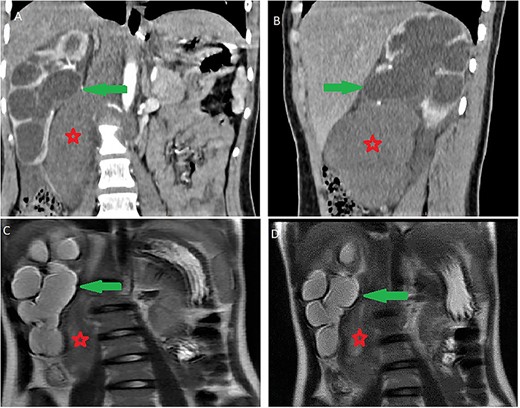

It was abutting the abdominal aorta, inferior vena cava and right renal pedicle. It extended toward the liver and right diaphragmatic pillar. It was compressing the kidney and ureter with ureterohydronephrosis and cortical thinning. Renal calyces and pelvis contents were dense and their walls enhanced (Fig. 3). The adrenal gland was normal.

Ureterohydronephrosis due to the mass effect; ureterohydronephrosis (green arrow) due to the mass effect (red spark) on coronal (A), sagittal (B) Ct scan and coronal MRI T2-weighted image (C and D).